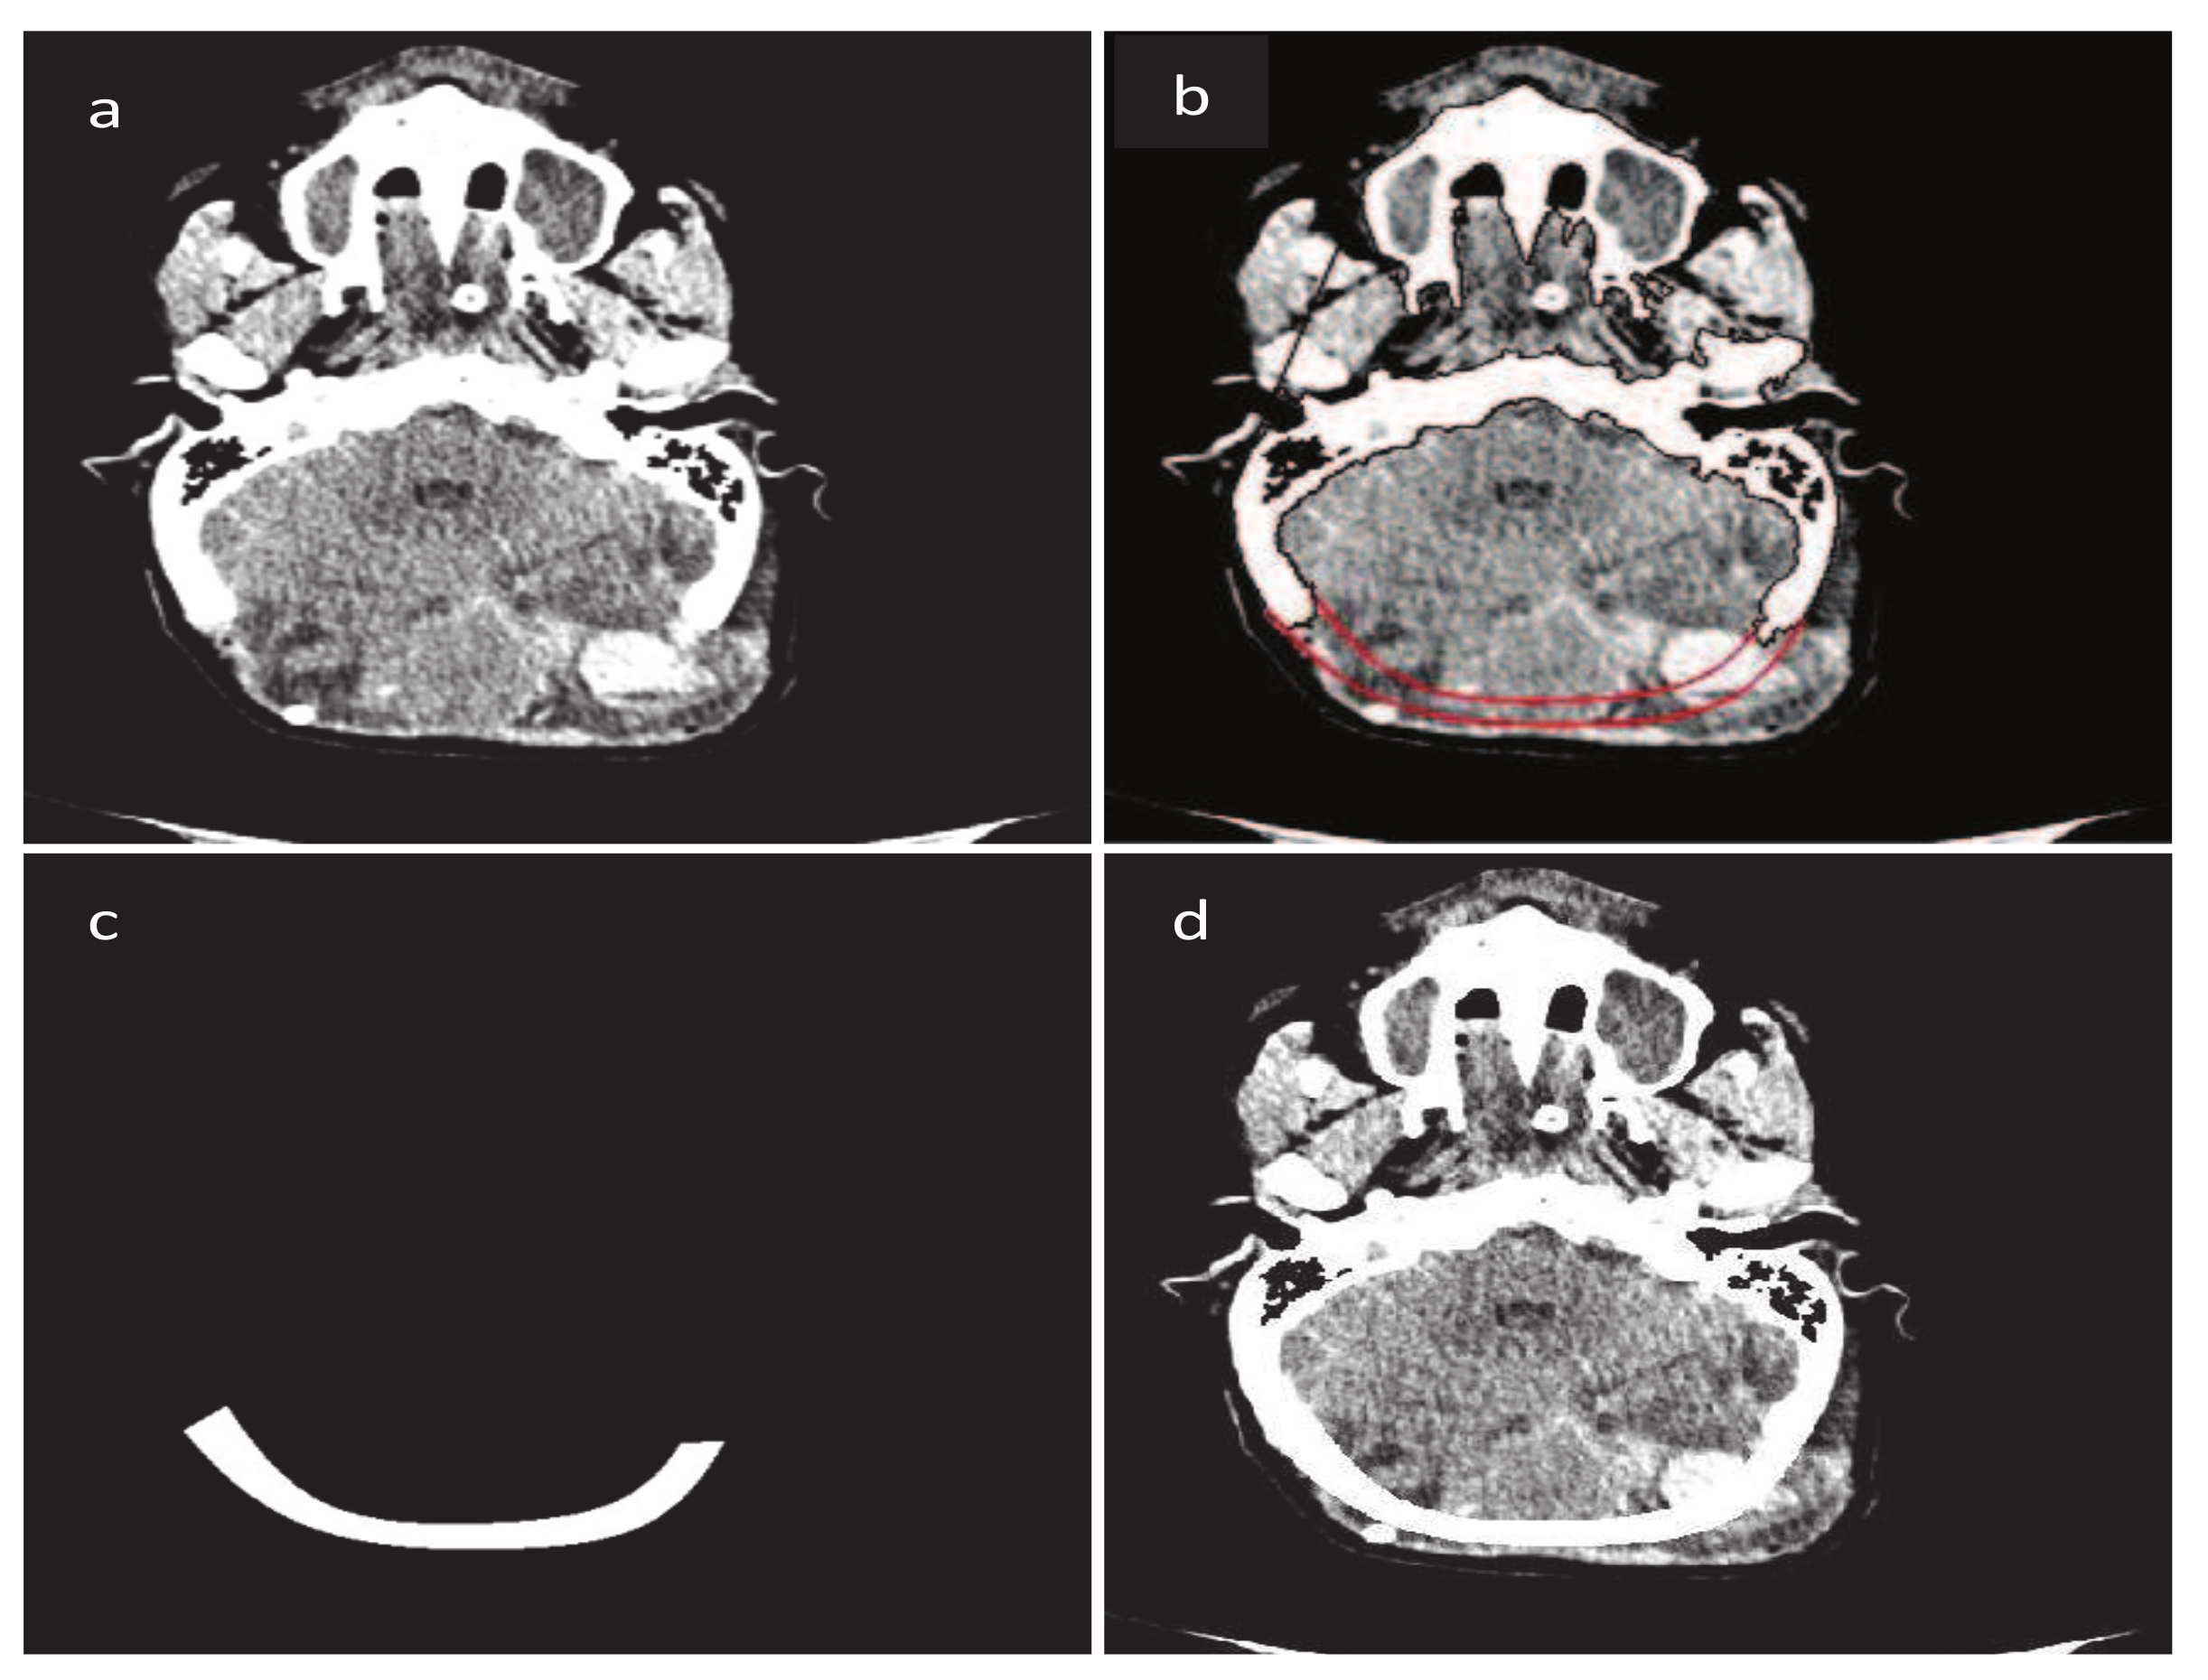

- Majeed, A.; Abbas, M.; Miura, K.T.; Kamran, M.; Nazir, T. Surface modeling from 2D contours with an application to craniofacial fracture construction. Mathematics 2020, 8, 1246. [Google Scholar] [CrossRef]

- Majeed, A.; Mt Piah, A.R.; Yahya, Z.R.; Abdullah, J.Y.; Rafique, M. Construction of occipital bone fracture using B-spline curves. Comput. Appl. Math. 2018, 37, 2877–2896. [Google Scholar] [CrossRef]

- Majeed, A.; Mt Piah, A.R.; Ridzuan, Y.Z. Surface Reconstruction from Parallel Curves with Application to Parietal Bone Fracture Reconstruction. PLoS ONE 2016, 11, e0149921. [Google Scholar] [CrossRef] [PubMed]